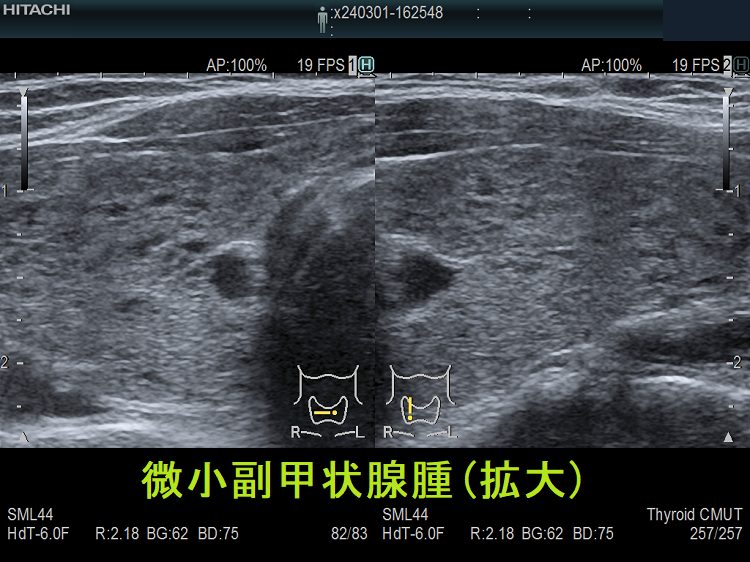

微小副甲状腺腫;血清カルシウムは正常範囲内の上限だが、脱水などの影響で上限を超える場合もある。骨密度は正常で、腎結石(腎臓結石)もない。

血清カルシウム・リン値正常、副甲状腺ホルモン(PTH)濃度も正常の副甲状腺腺腫が存在します。甲状腺超音波(エコー)検査で偶然見つかるケースがほとんどで、さほど大きくないためCT/MRIでは見えない場合が多いです。もちろん、副甲状腺機能亢進していないため治療適応にはなりません。副甲状腺ホルモン(PTH)合成能が低い副甲状腺腺腫ですが、年次フォローするとサイズが増大して、高カルシウム血症・副甲状腺機能亢進症に進展することもあります。[World J Surg. 2017 Jan;41(1):122-128.][Aust N Z J Med. 1998 Apr;28(2):173-8.]

甲状腺内副甲状腺腫は、超音波(エコー)検査で甲状腺腫瘍と形態的に鑑別できない場合があります(実際は下の写真のように診断できていますが・・)。特徴的な超音波(エコー)所見は、腹側の高エコーで感度86%、特異度100%です[Surgery. 2012 Dec;152(6):1193-200.]。さらに、99m-Tc MIBIシンチグラフィーで取り込み(集積)があれば甲状腺内副甲状腺腫と診断できます。